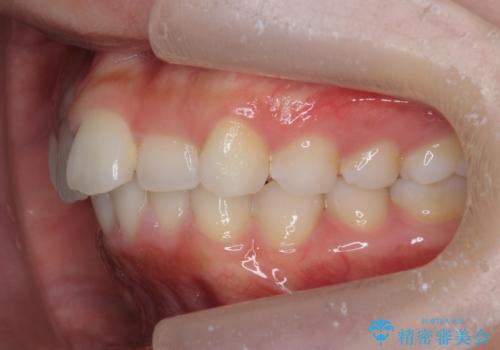

前歯のがたつき気になる。インビザラインモデレート

- 前歯のがたつきが気になるとの事で来院。

噛み合わせを確認したところ上の歯が全体的に前にある状態でした。

患者様は2のプランを選ばれたのでインビザラインモデレートで治療を行いました。

ガタつきがなくなり満足して頂けました。